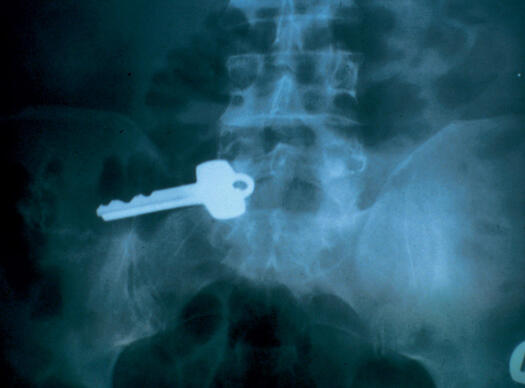

ЕКСПОНАТ 7

Ключ в корема

За жалост тук информация липсва. Кой е този хитър Буратино – никой не знае...